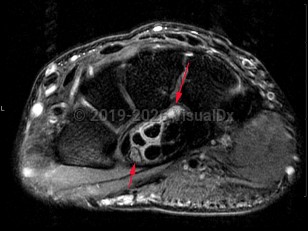

Mild carpal tunnel syndrome is typically not associated with dermatologic findings. When long-standing, autonomic nerve dysfunction occurs, resulting in necrotic carpal tunnel syndrome. Dermatologic manifestations will then include bullae, ulcers, hypohidrosis, vasospasm, and Raynaud phenomenon. Nail changes may also occur and may be a clue to diagnosis of carpal tunnel syndrome.